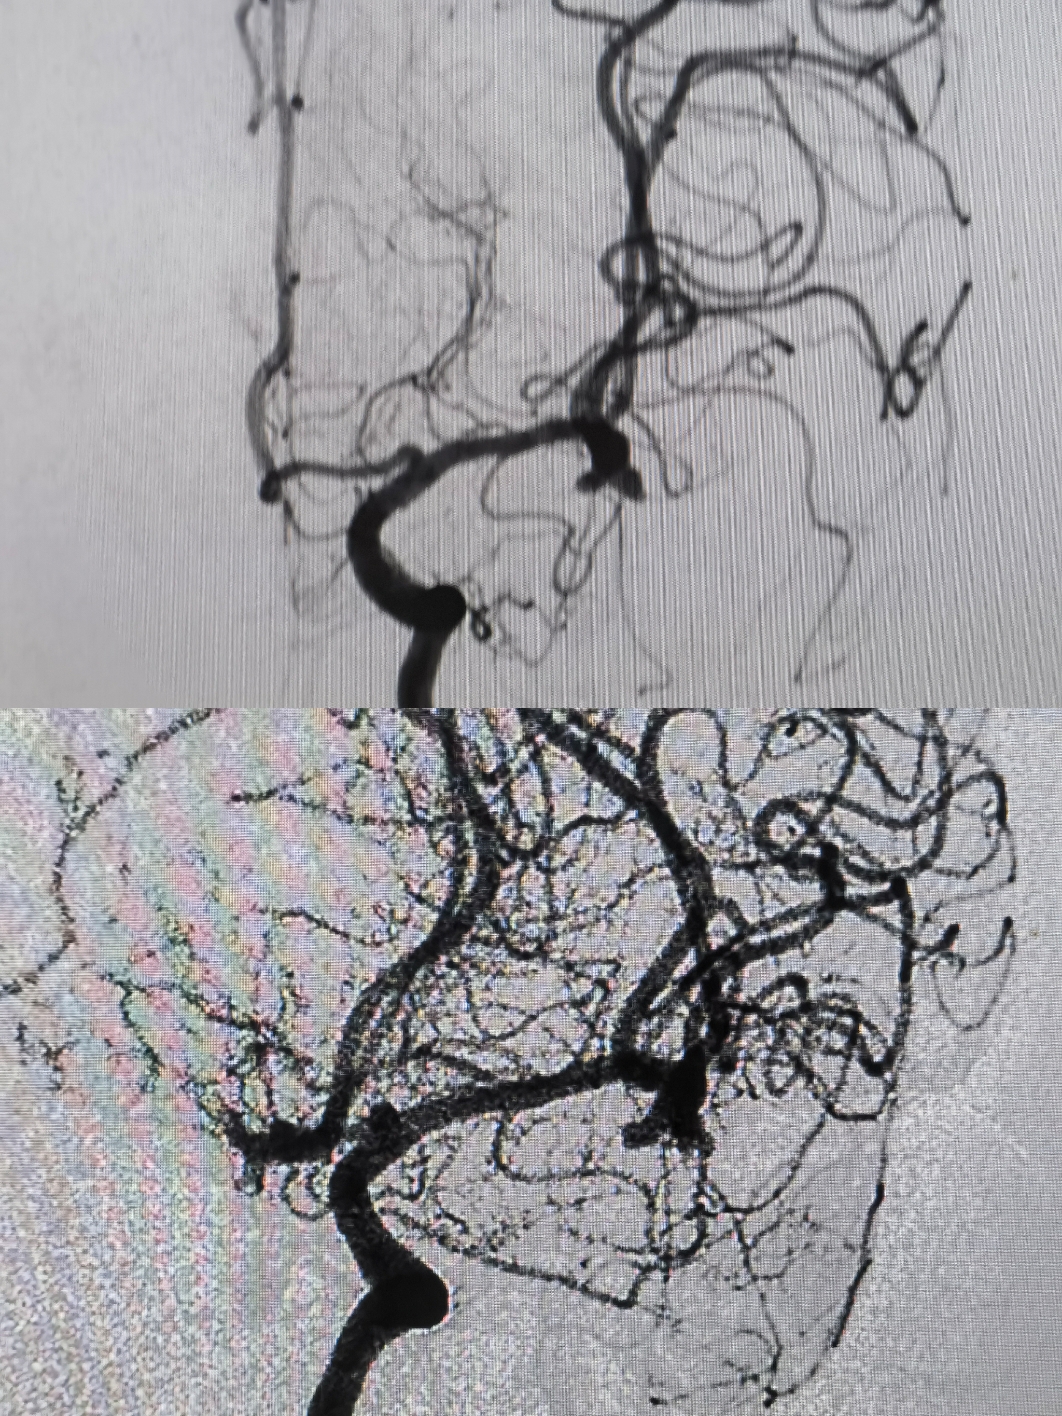

病例3左侧大脑中分叉部动脉瘤

患者头疼1周余入院,CT提示左侧颞叶血肿,入院神智嗜睡,GCS14分,四肢肌力正常

因头疼1周余就诊,行头颅CT提示左侧颞叶血肿,CTA提示左侧大脑中动脉瘤。神智嗜睡,GCS13-14分,首选开颅血肿清除+夹闭动脉瘤。患者家属反复拒绝开颅。

术前造影

术前3D情况

手术计划:三系统,支架导管放置上干,双微管栓塞

工作位,支架导管+双微导管到位情况

栓塞过程:双微管分区栓塞

栓塞术后情况

栓塞术后3D重建